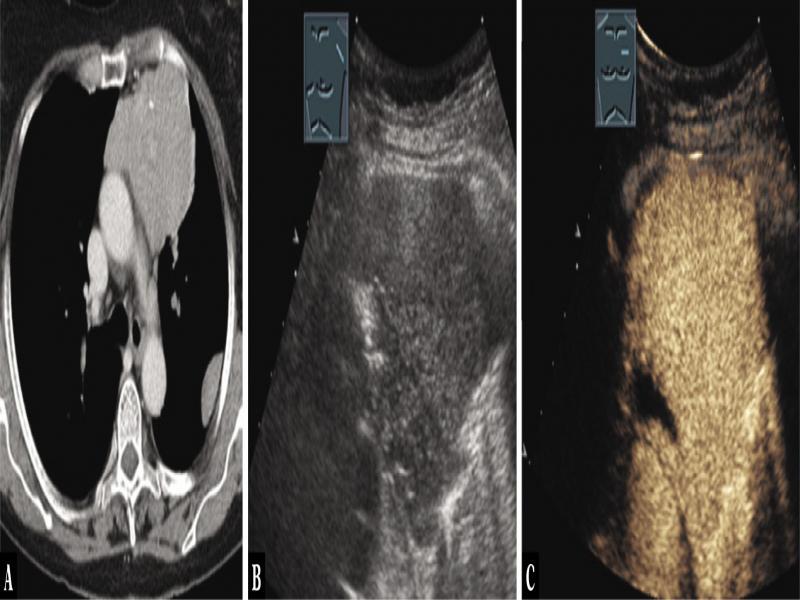

Fig. 1.

A 40-year-old female patient with mediastinal tumor in the anterior mediastinum as an incidental finding in computed tomography (A). Thoracic ultrasound indicated anechoic nodes (B), which showed no enhancement on contrast-enhanced ultrasound (C). Mediastinoscopy was performed, and regressive thymoma was histologically confirmed